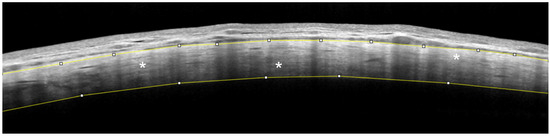

AS-OCT of the Sclera